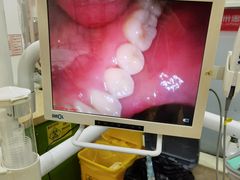

• 惠州口腔医院(下埔总院)

• -惠州口腔医院(下埔总院)